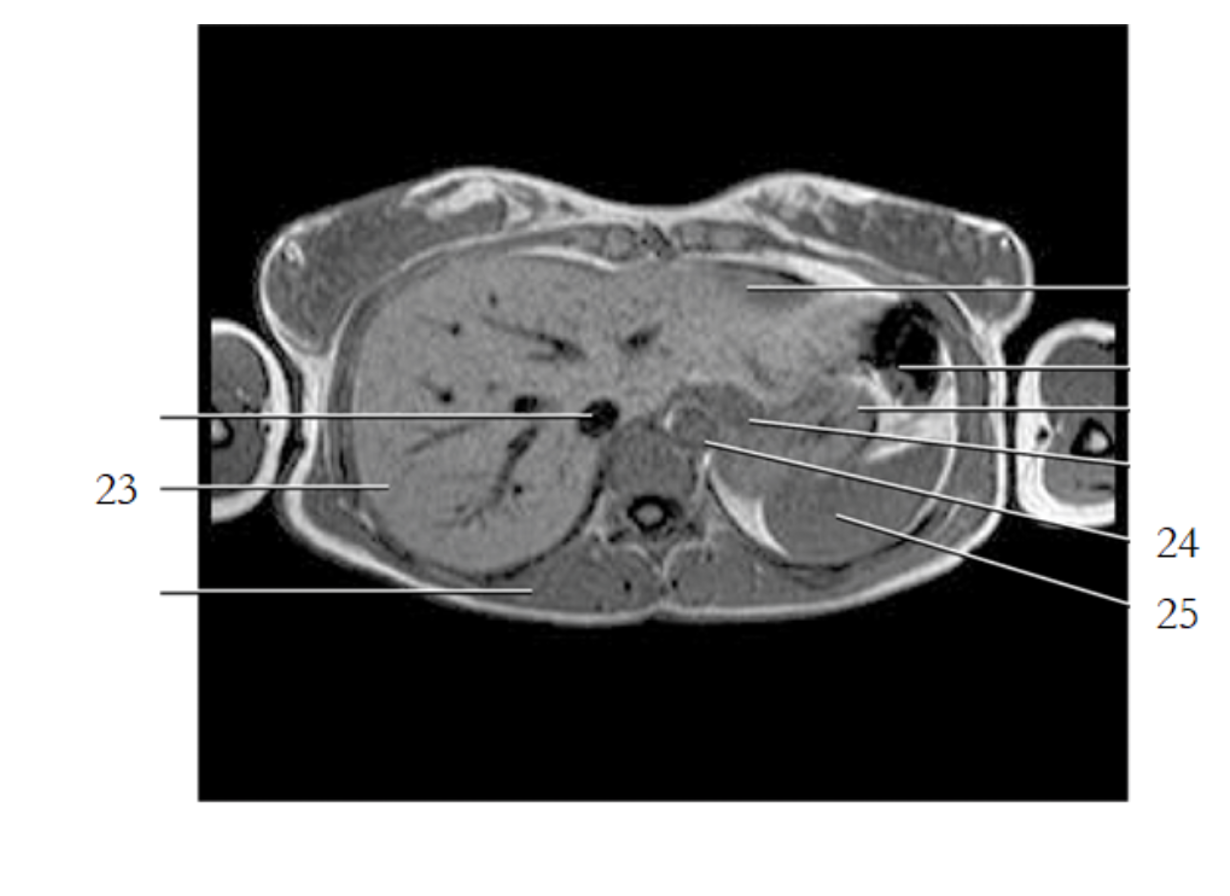

liver

spleen

IVC

pancreas tail

kidney

gallbladder

left renal artery

small bowel

large bowel